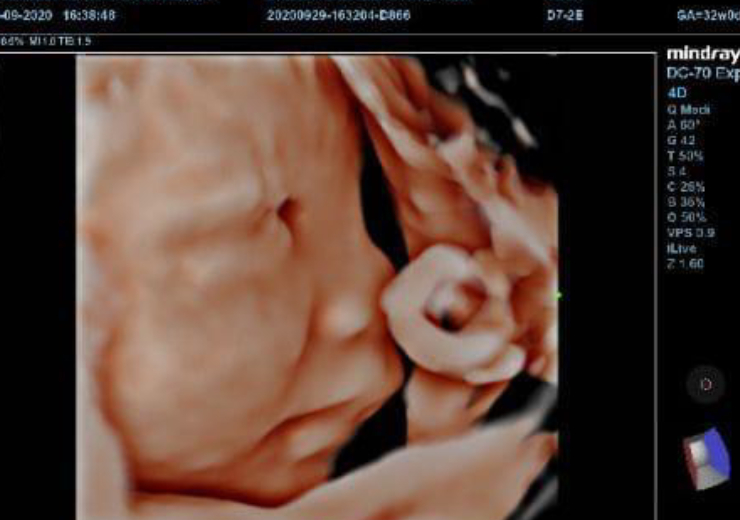

Control de Embarazo en Veracruz

Consulta integral durante todo el embarazo, realización de ultrasonido obstétrico.